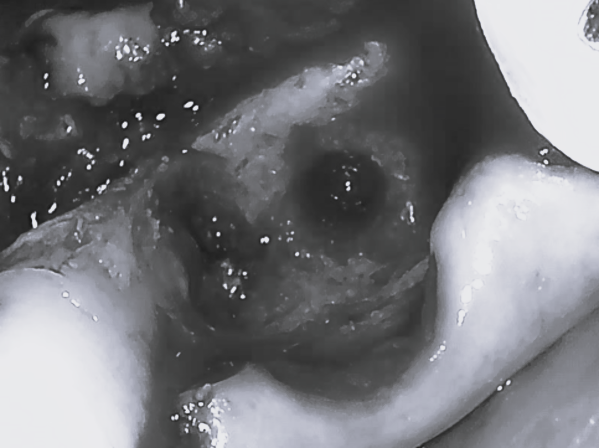

被せ物を外したところ、すでに出血や排膿が著しい状況でした。

インプラント撤去後、周りの組織を清掃しつつ、骨補填材による骨造成(GBR:Guided Bone Regeneration)を行います。

今回は5番の再生療法も同時に行っているため、刺激を避ける目的で被せ物も除去しています。